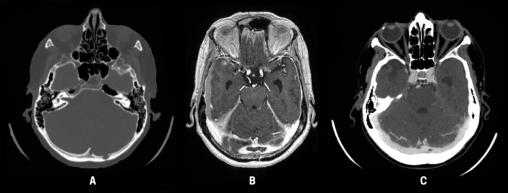

Un scanner cérébral sans injection montre des hématomes sous-duraux bilatéraux récents, une fracture occipitale gauche et une hypodensité cérébelleuse gauche. Cette fracture occipitale est directement au contact du sinus transverse gauche mais n’est pas, à proprement parler, une fracture trans-sinusienne (fig. A).

Un deuxième scanner cérébral avec injection ainsi qu’une IRM injectée révèlent une thrombose au niveau du torcular, étendue aux deux sinus transverses et un infarctus veineux cérébelleux gauche (fig. B).

La tomodensitométrie de contraste de suivi à trois mois a montré une régression complète de la thrombose, soutenant l’hypothèse post-traumatique (fig. C). Une hypodensité parenchymateuse séquellaire cérébelleuse gauche persiste.